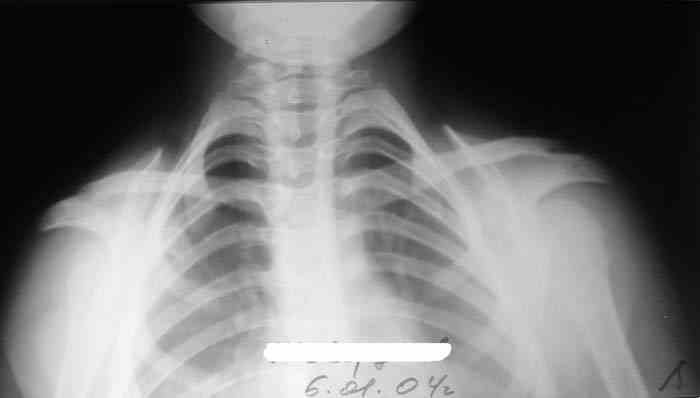

Девочка, 9 лет. Жалобы на деформацию верхнего плечевого пояса.

Объективно: приведение обоих надплечий, объем движений в плечевых суставах в полном объеме, общесоматический статус без патологии, УЗИлопаточных областей - без патологии.

Возможно речь идёт о добавочных шейных рёбрах, для уточнения целесообразно сделать боковую рентгенографию.

Hi! There are some winging of scapulae as at Long thoracic nerve pulcy.May be EMG will be helpfull

По МКБ-10 шейное ребро С6;С7. Вот ссылка:http://www.ristar.ru/info/references/mkb/1385/1448/1460

Боковая рентгенография обязательно. Устранение деформации возможно только оперативным путём. Никакая физиотерапия ничего не даст...

Больная на Вашей фотографии довольно похожа на Cleidocranial Disostosis. Пришлите снимки плечевого пояса. Это может быть недоразвитие или отсутствие ключиц.

Наличие ключиц на прямом снимке, снимает диагноз врожденного отсутствия ключиц.

Мне кажется, случай похож на Poland's Syndrom, синдром встречается при врожденной паталогии, когда отсутствует грудные мышцы (pectoralis), в большинстве случаев односторенне, и пластические хирурги рекомендует операцию.

Предлагаю пока рабочим диагнозом считать: "Врожденная аномалия грудной клетки. Добавочные шейные ребра".